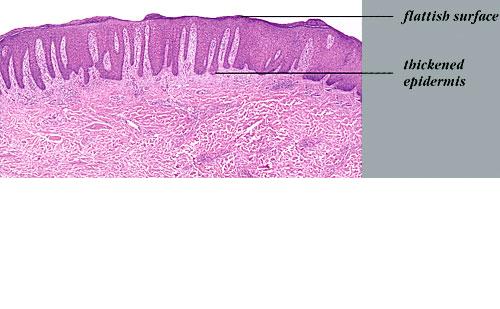

exocytosis of neutrophils, they may aggregate in the uppermost portion of the spinous layer to form small spongiform pustules of Kogoj. Lymphocytes remain confined to the lower epidermis, which, as more and more mitoses occur, becomes increasingly hyperplastic. The epidermal changes are at first focal, but later become confluent, leading clinically to plaques. In the fully developed lesions of psoriasis, as best seen at the margin of enlarging plaques, the histologic picture is characterized by (a) acanthosis with regular elongation of the rete ridges with thickening in their lower portion; (b) thinning of the suprapapillary epidermis with the occasional presence of small spongiform pustules; (c) pallor of the upper layers of the epidermis; (d) diminished to absent granular layer; (e) confluent parakeratosis; (f) the presence of Munro microabscesses; (g) elongation and edema of the dermal papillae; and (h) dilated and tortuous capillaries . |

The rete ridges show considerable elongation and extend downward to a uniform level, resulting in regular acanthosis . They are often slender in their upper portion but |

show thickening ("clubbing") in their lower portion. Not infrequently, adjacent rete ridges seem to coalesce at their bases due to tangential sectioning. Usually, intercellular and intracellular edema is absent in the rete ridges, and keratinocytes located well above the basal layer show deep basophilia. In addition, mitoses are not limited to the basal layer as in normal skin but are also seen above the basal layer. This, together with a considerable lengthening of the basal cell layer due to elongation of the rete ridges, results in a marked increase in the number of mitoses. This increase has been calculated to be 27 times the number of mitoses in uninvolved skin . |

The suprapapillary epidermis appears relatively thin in comparison with the markedly elongated rete ridges, and the cells in the upper layers of the epidermis may appear enlarged and pale stained as a result of intracellular edema and hypogranulosis. Keratinocytes beneath the parakeratotic cornified layer may be intermingled with neutrophils . The histologic picture is then that of a small spongiform pustule of Kogoj . Although it is only a micropustule, it is nevertheless of the same type as the much larger macropustules seen in pustular psoriasis. Such a spongiform pustule, highly diagnostic for psoriasis and its variants, shows aggregates of neutrophils within the interstices of a spongelike network formed by degenerated and thinned epidermal cells |